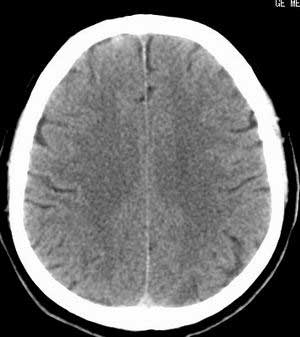

患者男,58岁。耳爆震伤后耳聋2年余,而后双耳道肿胀,间断性流脓。近一月来头痛、恶心、呕吐,右眼红痛,不能入眠。

在平扫时,见右侧枕骨下方小脑半球表面带状模糊稍高密度影,考虑为耳源性脑内感染。

脑实质密度均匀,未见异常密度灶,脑沟裂池室形态大小正常,中线结构居中.

双侧乳突蜂房密度呈气体样,慢性乳突炎可能性不大,

双侧颞叶脑实质密度均匀未见异常密度灶,

考虑颅内未见异常。

平扫右侧岩骨与枕骨交角内侧脑质内见淡片状密度增高影,内缘清晰。增强图象上未见明显显示。

考虑:1)伪影可能,建议复查头ct平扫。

2)加照头ct骨窗,以显示乳突气房内是否有病变。